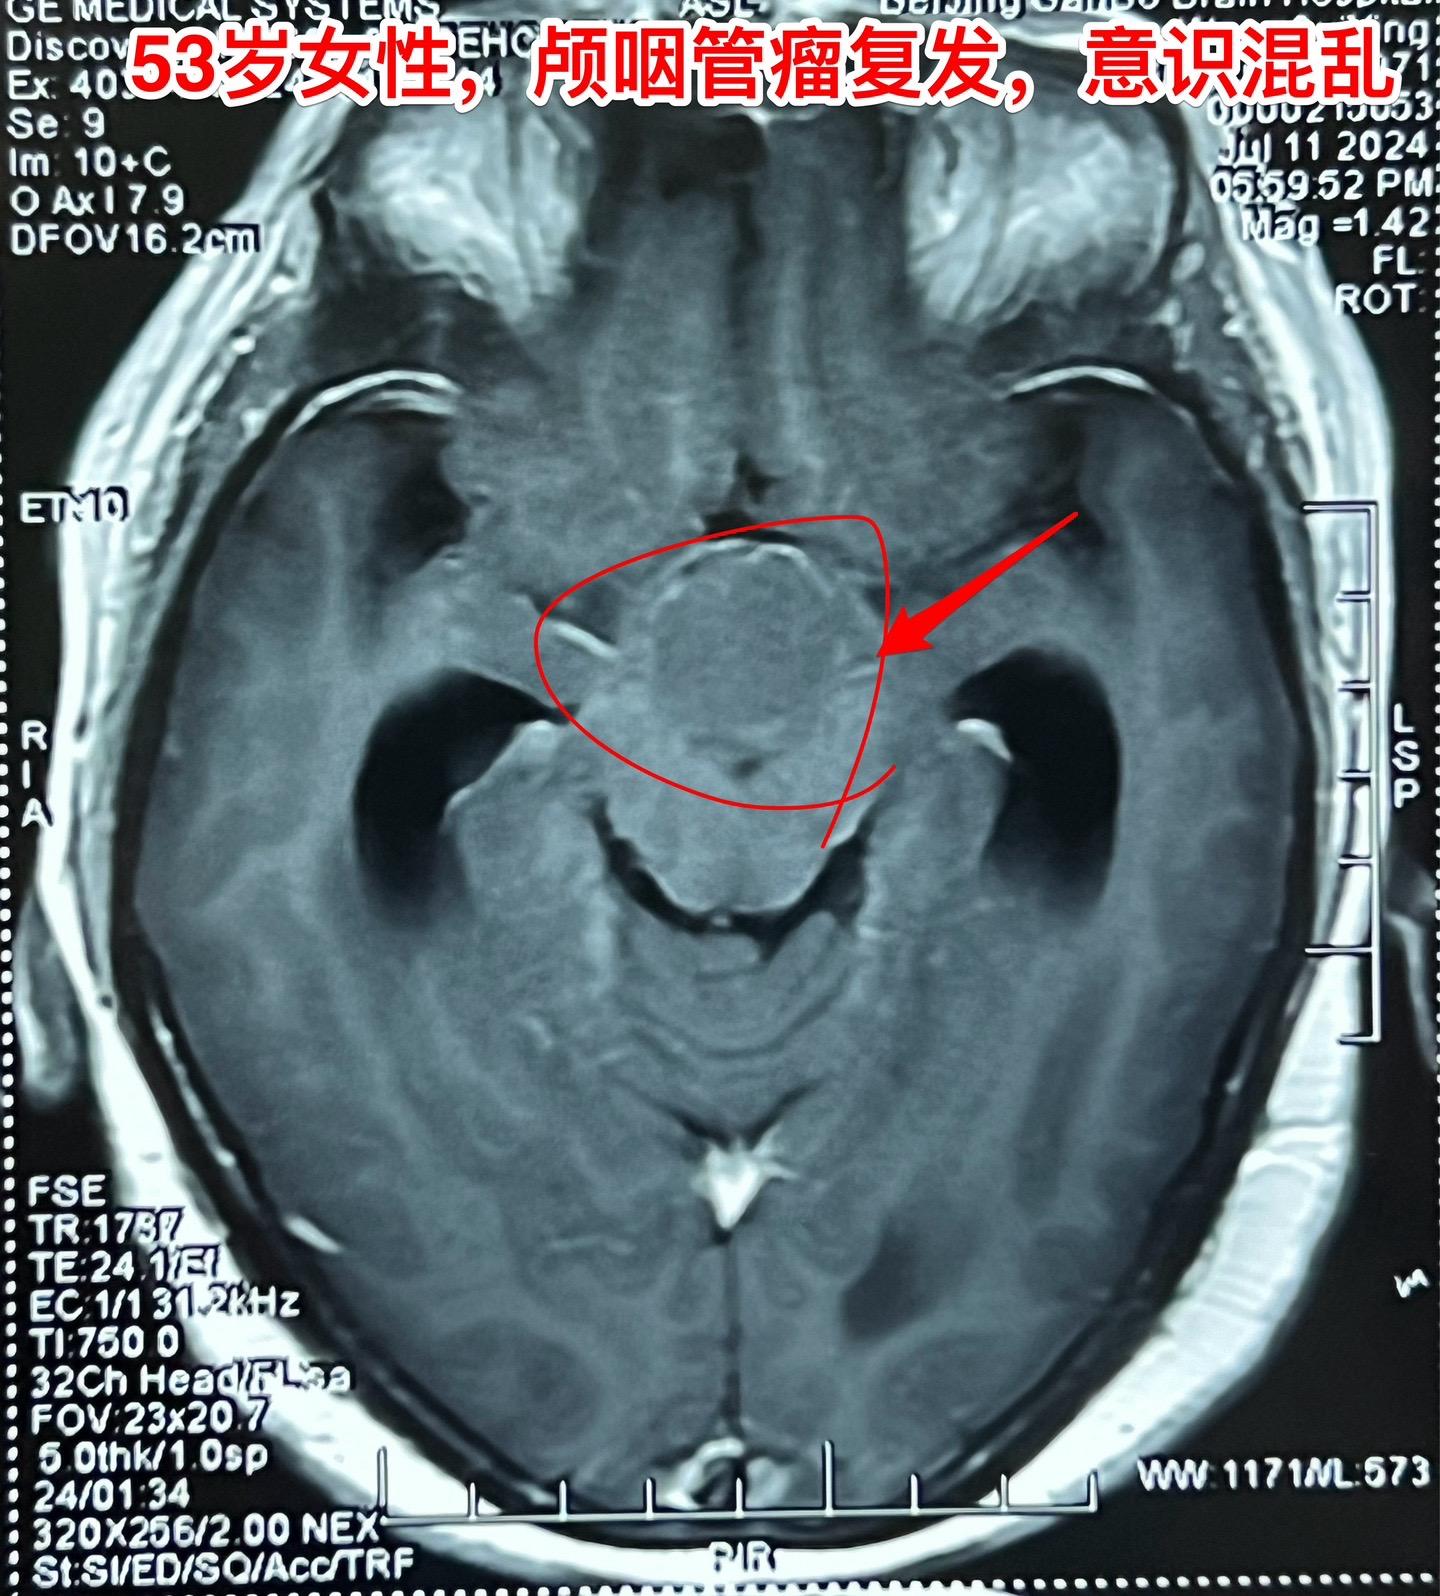

颅咽管瘤复发了怎么就意识混乱了?安徽省宿州的女性,53岁,14年前曾经作过颅咽管瘤切除手术。近10天她突然出现意识混乱,胡说,尿失禁,行走不稳。这是为什么呢? 其实她的病并不突然。 14年前作过颅咽管瘤切除手术,肿瘤有残留,就作了伽马刀治疗。2015年肿瘤复发了,又作了一次伽马刀治疗。之后生活质量还不错,能够作家务。 住院前10天她突然出现意识混乱,胡言乱语,同时还有尿失禁,行走困难。到医院去作头C T检查,发现肿瘤复发了,而且还造成了脑积水。